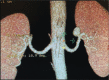

Computed tomography angiogram demonstrating aneurysm at the left renal artery.